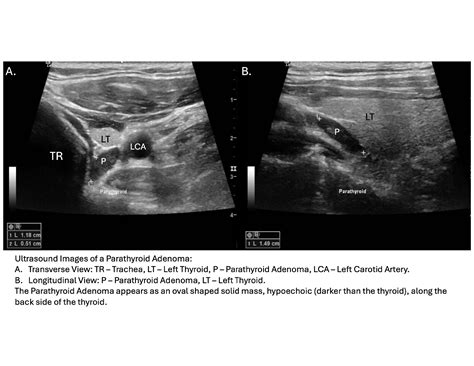

Interpreting the results of parathyroid gland sonography requires expertise in radiology and endocrinology. The images obtained during the procedure are analyzed for several key features:

• Size and shape of the parathyroid glands.

• Presence of any nodules or masses.

• Location of the parathyroid glands relative to the thyroid gland.

• Blood flow patterns within the glands, which can indicate the presence of tumors.

Abnormal findings may include enlarged parathyroid glands, the presence of adenomas, or other structural abnormalities. These findings are crucial for diagnosing conditions such as primary hyperparathyroidism, secondary hyperparathyroidism, and parathyroid carcinoma.

Parathyroid Adenomas Benign tumors within the parathyroid glands. Primary Hyperparathyroidism